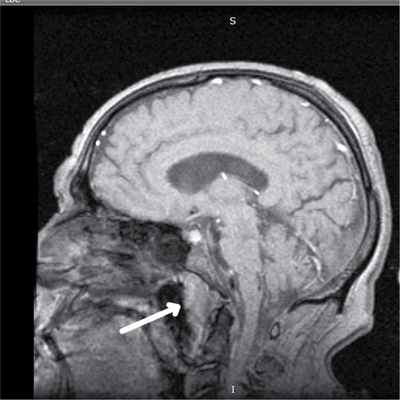

Для уточнения степени распространения опухоли, определения деструктивных изменений черепа, вовлечения в процесс черепно-мозговых нервов, исключения опухолей головного мозга, распространяющихся в носоглотку, необходимо выполнить спиральную рентгеновскую компьютернную томографию [11] или конусно-лучевую компьютерную томографию (3D). Диагностическую ценность представляют магнитно-резонансная томография, ПЭТ-КТ (рис. 3).

Рис. 3. МРТ-исследование головы в сагиттальной проекции. Новообразование носоглотки (стрелка).